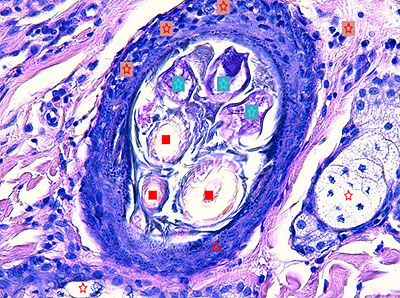

Photo 6 : (Hémalun-Eosine – X400) : Vue rapprochée d’un canal sébacé

permettant de visualiser son hyperplasie et son hyperkératose orthokératosique,

la distension kystique de la glande sudorale épitrichiale et l’inflammation péri-isthmique

lympho-plasmocytaire et discrètement mural au sein de la paroi du canal sébacé.

Légendes de la Photo 6 :

- Étoile turquoise = paroi du canal sébacé hyperplasique

- Flèche double noire = lobules de glande sébacée

- Flèche double bleue = tige pilaire dans un isthme folliculaire

- Carré rouge = infiltrat inflammatoire lympho-plasmocytaire péri-isthmique pénétrant discrètement la paroi épithéliale du canal sébacé

- Étoile rouge = lumière du canal sébacé siège d’une hyperkératose orthokératosique

- Étoile noire = lumière kystique d’une glande sudorale épitrichiale (portion fundique)

Photo 7 : (Hémalun-Eosine – X400) : Vue rapprochée d’un isthme folliculaire permettant

de visualiser une inflammation murale lymphocytaire et la lumière folliculaire contenant

trois silhouettes parasitaires démodéciques.

Légendes de la Photo 7 :

- Étoile turquoise = trois silhouettes parasitaires démodéciques dans la lumière folliculaire

- Carré rouge = tiges pilaires

- Étoile rouge = infiltrat inflammatoire lymphocytaire mural dans la paroi de la gaine épithéliale folliculaire externe et plasmocytaire au pourtour de l’isthme folliculaire

- Étoile rouge = lobules de glande sébacée hyperplasique

- Pointe de flèche rouge = gaine épithéliale folliculaire externe d’un follicule pileux

Photo 8 : (Hémalun-Eosine – X1000, huile à immersion) :

Vue au fort grossissement d’un canal sébacé contenant une silhouette de Demodex.

Légendes de la Photo 8 :

- Étoile turquoise = silhouette parasitaire démodécique dans la lumière du canal sébacé

- Carré rouge = lumière du canal sébacé

- Étoile rouge = sébocytes matures

- Pointe de flèche rouge = cellules de réserve (blastème) d’un lobule de glande sébacée hyperplasique